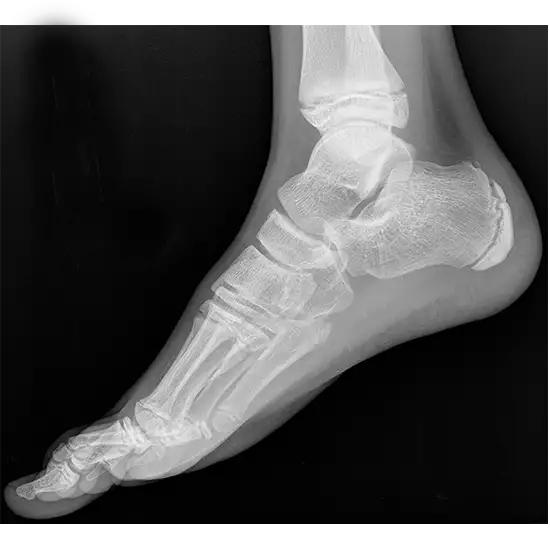

An X-Ray Right Foot LAT View is a safe and painless test that uses a small amount of radiation to see the bones of the foot, such as the ankle bones (tarsal bones), the front of the feet (metatarsal bones), and the toes (phalanges), as well as the soft tissues (skin and muscles) that surround them.

The test shows if any bones in the foot are broken or fractured. It checks how well they are healing after being set and looks for infection, osteoporosis, abnormal bone growth, deformities, or arthritis.